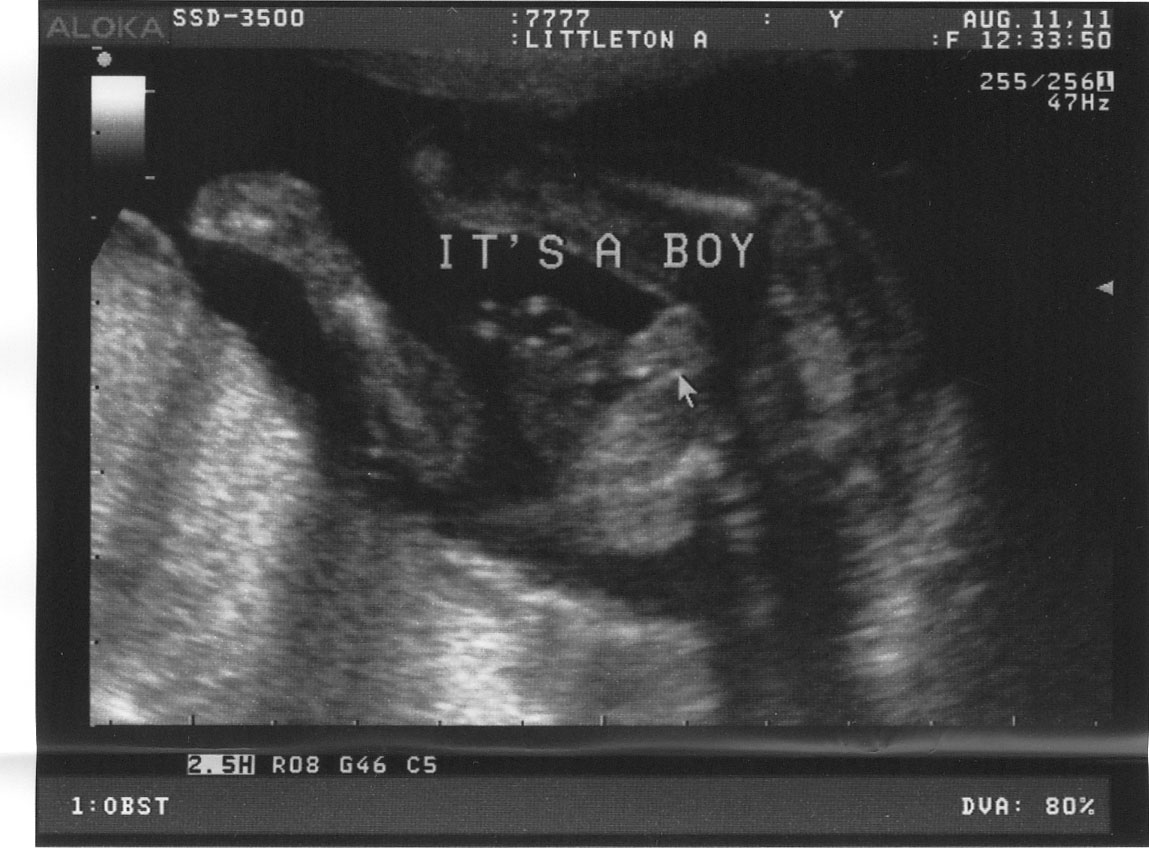

On Thursday we found out that new baby (code name #2) is going to be a boy! A few ultrasound pics below. You can apparently tell from the one with the “Its a Boy” on it that he is in fact a boy – but I couldn’t tell until the tech wrote out the text. If you can tell, I think you missed your calling as an ultrasound technician :)